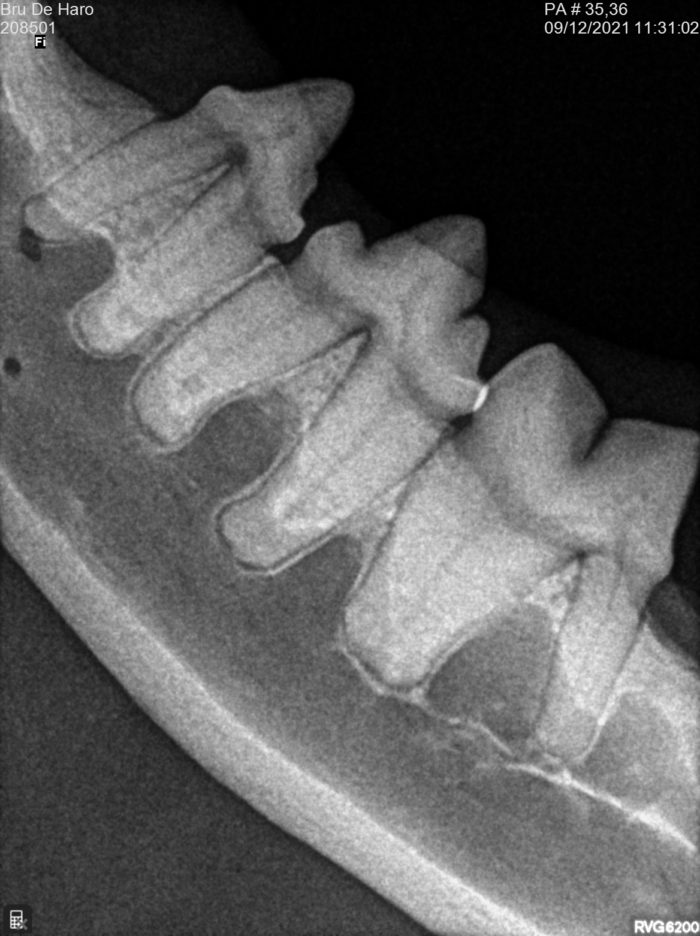

Odontologia veterinària

El servei d’odontologia inclou radiologia dental intraoral digital, fonamental per a una bona praxi en odontologia veterinària.